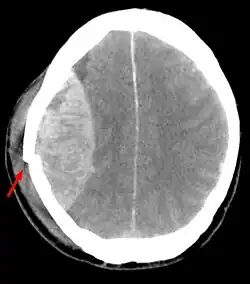

Los hematomas intracraneales se clasifican de acuerdo a su localización en epidurales, subdurales e intraparenquimales.[15]

Los hematomas epidurales son los que se localizan entre la lámina interna craneal y la duramadre. Como se ha mencionado están asociados con fracturas de cráneo y ruptura de la arteria meníngea media o sus ramas. Son más comunes en las regiones parietales y temporales y son raros en las regiones frontales y occipitales. Se encuentran entre el 8% y 10% en pacientes con TCE grave. En la TAC, se ven como lesiones hiperdensas y biconvexas y debido a que no existe un espacio entre la duramadre y el hueso no suelen propagarse a menos que superen la adherencia de la duramadre. Estos hematomas son raros en infantes debido a que el cráneo es deformable lo que les confiere una protección. Además son raros en adultos mayores de 60 años debido a la adherencia débil de la duramadre al cráneo.[15]

Los hematomas subdurales se encuentran entre la cara interna de la duramadre y la superficie cerebral. Se encuentra entre el 20% y el 25% en pacientes con TCE grave. Son el resultado de hemorragia en las venas anastomóticas de la corteza cerebral superficial o ruptura de los senos venosos o sus tributarios y se asocian con daño en el tejido cerebral subyacente. Más específicamente se ha demostrado que un buen número de estos hematomas se deben a la ruptura de venas puente parasagitales.[31][32] Normalmente se expanden en la mayor parte de la convexidad cerebral pero no pueden propagarse al hemisferio contrario debido a la existencia de la hoz del cerebro. Los hematomas subdurales se clasifican en agudos, subagudos o crónicos dependiendo de la aparición y duración de estos y su aspecto característico en la TC:[15]

- Hematomas subdurales agudos: se observan hasta los 3 días de la lesión y en una TC su aspecto es de manchas con color blanco brillante.

- Hematomas subdurales subagudos: se observan desde los 3 días hasta las 3 semanas del trauma y su aspecto en TC es isodenso con relación al tejido cerebral, usualmente se confunden y son pasados por alto.

- Hematomas subdurales crónicos: se producen desde las 3 semanas hasta los 3 meses después del trauma y su aspecto en TC es hipodenso con relación al tejido cerebral.